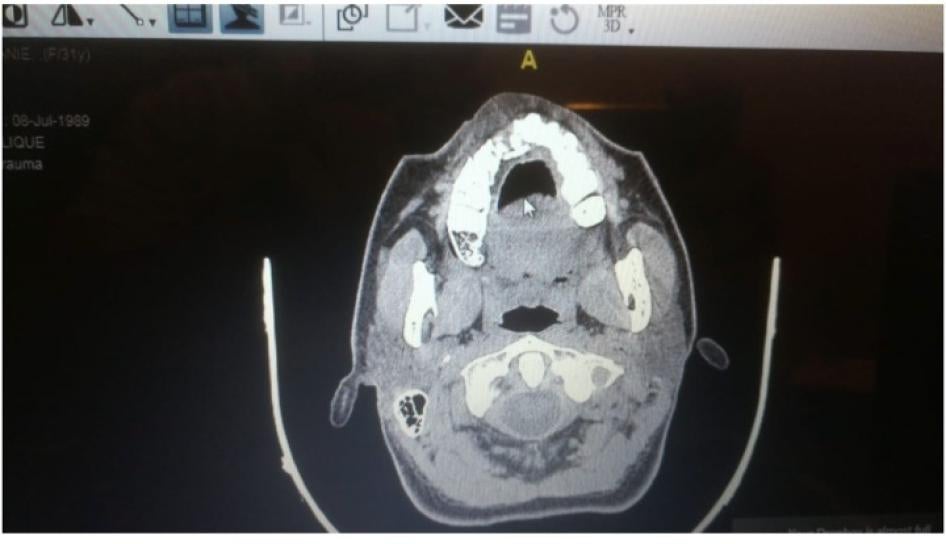

Another doctor shared the anonymized X-rays of a patient who was wounded by dozens of pellets. The doctor said that the number of pellets and the fact that they punctured the patient’s scalp indicate that security forces shot at the person’s face from a very short distance. The pellets embedded under the sinus in the skull and in the protester’s eye, the doctor said.

Dozens of pellets wounded this protester, puncturing their scalp and embedding under their sinus and in their eye. © 2020 Private